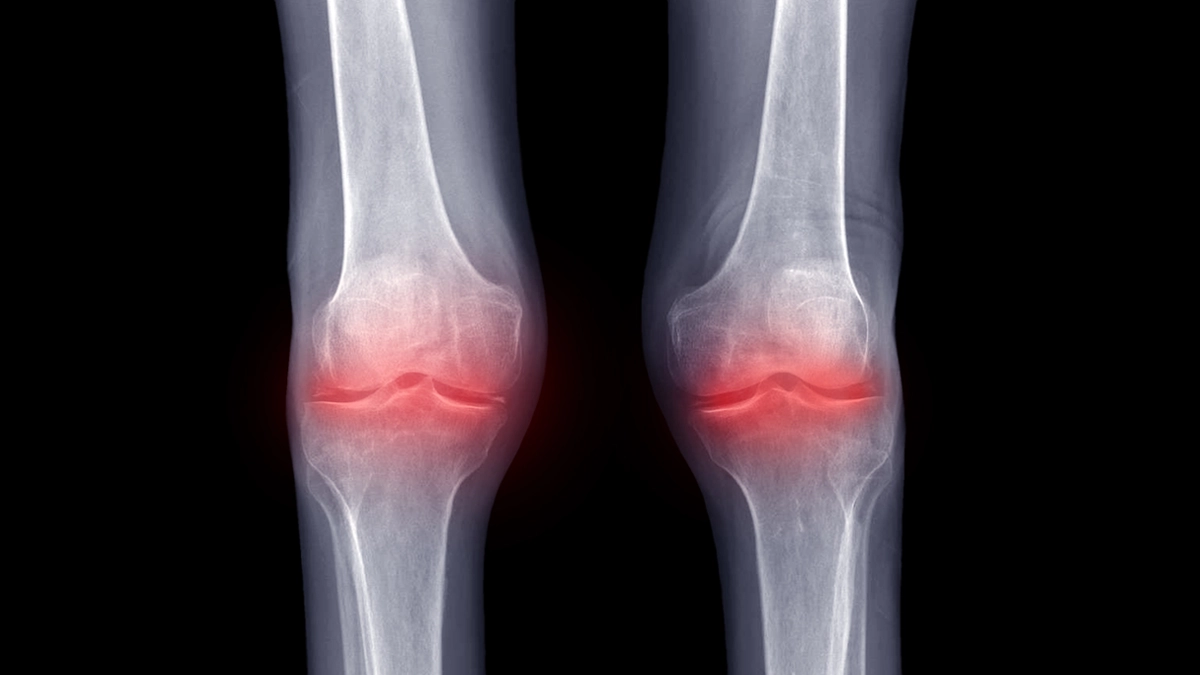

Klinik seyir, erken dönemde aktiviteyle artan mekanik ağrı ve başlangıç tutukluğu ile başlar. Uzun oturmadan kalkınca ilk adımlarda keskin bir ağrı, kısa yürüyüş sonrası akışkanlıkta artış tipiktir. Süreç ilerledikçe eklem aralığı daralır, hareket açıklığı (özellikle tam açma) azalır, krepitasyon ve aksama belirginleşebilir. Alevlenme dönemlerinde diz şiş ve gergin hissedilir; arka tarafta Baker kisti oluşabilir ve bu da baldır üstünde gerilme/çekilme hissi yaratabilir. Ağrı her zaman radyolojik bulgularla birebir orantılı değildir; film ağır, ağrı hafif ya da film hafif, ağrı belirgin olabilir. Bu yüzden tanıda öykü ve muayene esastır; radyoloji klinikle birlikte yorumlanmalıdır.

Diz Eklemi kireçlenmesi ; Tanısal yaklaşım, ayrıntılı öykü ve fizik muayene ile başlar. Muayenede eklem çizgisi hassasiyeti, fleksiyon–ekstansiyon kısıtı, kuadriseps zayıflığı ve propriyosepsiyon kaybı öne çıkar. Ağırlık taşıyan pozisyonda çekilmiş diz grafileri, eklem aralığı daralması, osteofit, subkondral skleroz ve kist gibi bulguları gösterir. MR, menisküs, bağlar ve kemik ödemi gibi yumuşak doku ayrıntıları gerektiğinde değerlendirir; fakat tedavi planı klinik uyum olmadan yalnız MR’a dayanmaz. Ayırıcı tanıda menisküs yırtığı (kilitlenme/takılma anları), patellofemoral ağrı sendromu, tendinitler, romatizmal artrit ve kristal artropatiler düşünülmelidir. Kızarıklık, belirgin ısı, ateş ile seyreden akut diz ağrısı, enfeksiyon açısından acil değerlendirme gerektirir.